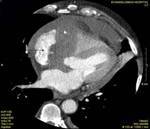

Background: Proper diagnosis of the type and extension of a cardiac tumor or mass is very important for therapy planning. Echocardiography has an established role as a non-invasive diagnostic imaging modality. Computed tomography (CT) and magnetic resonance imaging (MRI) also provide adequate delineation of cardiac tumors and masses.

Methods: Twenty-two patients referred to our department with a suspected cardiac mass, previously detected by cardiac ultrasound, were evaluated by CT (12 patients) and MRI (4 patients). Six patients were examined by both modalities. In 2 cases of staging of a known primary neoplasm and one case of a suspected epicardiac lesion, positron emission tomography (PET-CT) was performed. The CT cardiac examinations were performed using a 16-slice multislice scanner with ECG gating. The MRI examination was performed on a 1.5 Tesla MRI scanner using an ECG-gated cardiac protocol and the PET-CT examination was performed on an integrated PET-CT four-slice scanner, using 370 mMBq of fluorodeoxyglucose.

Results: Twenty-two cardiac masses were successfully detected and their characteristics adequately delineated, including eight myxomas, one angiosarcoma, one ventricular lymphoma, one endocardiac metastasis, one epicardiac paraganglioma, and 10 cases of intracardiac thrombi.

Conclusion: CT and MRI are noninvasive imaging modalities which can delineate cardiac tumors and masses and provide essential information for adequate diagnosis, staging and treatment planning. Compared to cardiac ultrasound, CT and MRI are superior in preoperative planning.